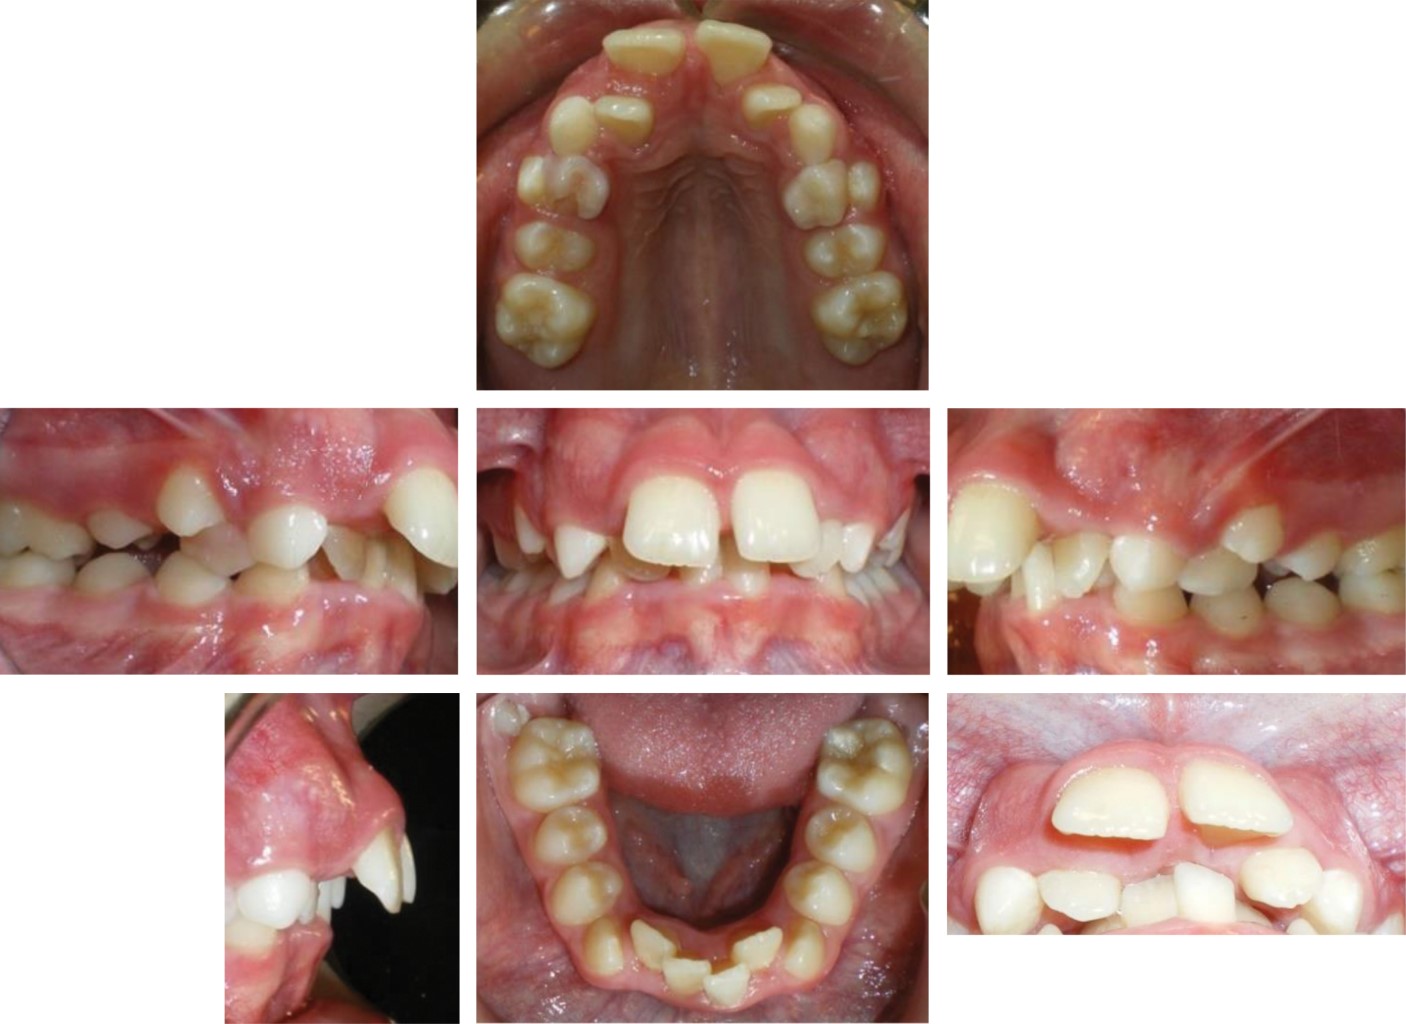

Paciente con antecedentes de problemas respiratorios, hiperdivergente, clase II esquelética, plano oclusal inclinado, perfil convexo, apiñamiento dental superior e inferior, clase II molar, incompetencia labial severa de 11 mm, mordida profunda anterior de 8 mm, mentón retrusivo -17 mm, posterorotación mandibular, plano mandibular inclinado, ángulo goníaco alto en relación a horizontal verdadera-stomion superior (Sts), antero rotación de cabeza, cervicales rectificadas, espacio entre C0 y C1 aumentado, espacio en C2 y C3 muy reducido5,6 (Figuras 1, 2, 3 y 4).

Figura 1